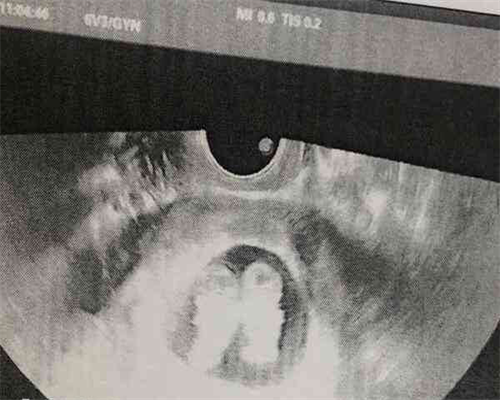

试管有没有1个卵泡成功的?试管有没有1个基础卵泡成功的案例?下面我们就来具体介绍下。

只有1个基础卵泡的做试管也有成功的案例,只要有排卵,就有希望。而且每个月的基础卵泡数量是不一样的,通过多次促排,是可以积累多个卵泡的,这样就会有多个胚胎,移植成功率也会有所保障。基础卵泡数量不代表成功率,卵子的质量才是重要的,只是说相对于卵泡多的患者,成功率是会低一些。

基础卵泡1个试管成功的情况

1. 即便只有1个基础卵泡,但是卵泡质量不错,一样能够增加只有一个卵泡移植的成功率;

2. 只有1个基础卵泡的情况下,患者自身的身体情况也是非常重要的,较好的身体条件只有一个卵泡也能成功。

所以说,基础卵泡只有1个做试管婴儿在卵泡质量高的情况下,成功率还是比较可观的。但这对患者的自身条件要求也较高,只有在身体素质好、卵泡质量高的情况下,一个基础卵泡才有可能移植成功。